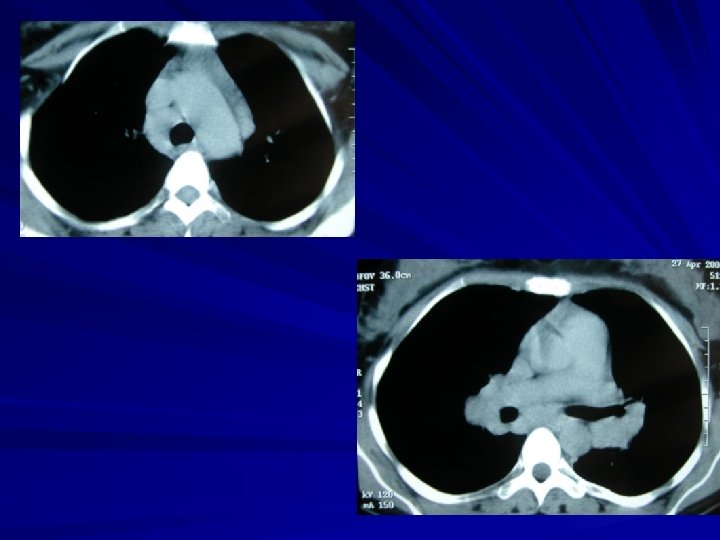

Plevral efüzyonda BT Çok duyarlı: minimal effüzyonlar saptanır Loküle effüzyonların saptanması Effüzyon – konsolidasyon ayrımı Ampiyem – apse ayrımı Nedeni ortaya koyabilir (pnömoni, malignansi, kalp yetmezliği, …) Benign – malign plevral hastalık ayrımı – %70 -80 doğruluk

Mediastinal kitleler Keskin sınırlı, mediasten ile geniş açı yapan, akciğere konveks Mediastinal kitlelerin: – %60 ön – %25’i orta – %15’i arka mediastende

Mediastinal kitle kuşkusunda yanıtlanması gereken sorular Gerçekten mediastende mi? Mediastenin hangi kompartmanında Karakterize edici özelliği var mı? (BT-MR) – Yağ dansitesi – Su dansitesi – Kalsifikasyon – Damarsal bileşen

Mediastende mi, akciğerde mi? Mediastinal kitle Akciğer kitlesi Hava bronkogramı (-) Hava bronkogramı (+/-) Mediasten kenarı ile açı geniş Mediasten kenarı ile açı dar Mediastinal çizgilerde bozulma (+) Mediastinal çizgilerde bozulma (-) Spinal veya sternal anormallik olabilir Spinal veya sternal anormallik beklenmez

Akciğer kitlesi (dar açı) Mediasten kitlesi (geniş açı)